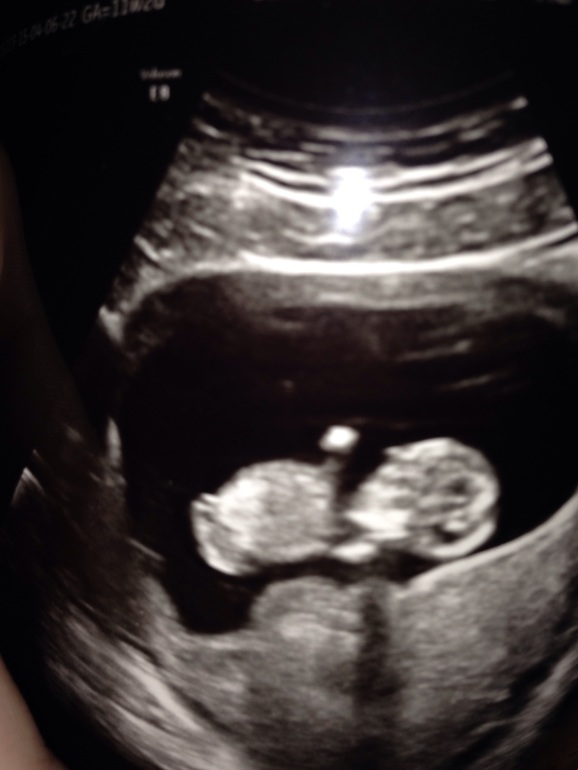

Вопросы про УЗИ, обследования и анализы: что, где, как, когда? была на скрининге в 11 недель. Так как он был бесплатный то длился ровно минуту и вердикт врача ПОКА все хорошо. Прям с таким акцентом. Получила я первое фото ляли. Муж как маленький надеялся пол узнать))) естественно рано) смотрит теперь и гадает кто же. во сколько недель вам сказали пол? Ну и фото